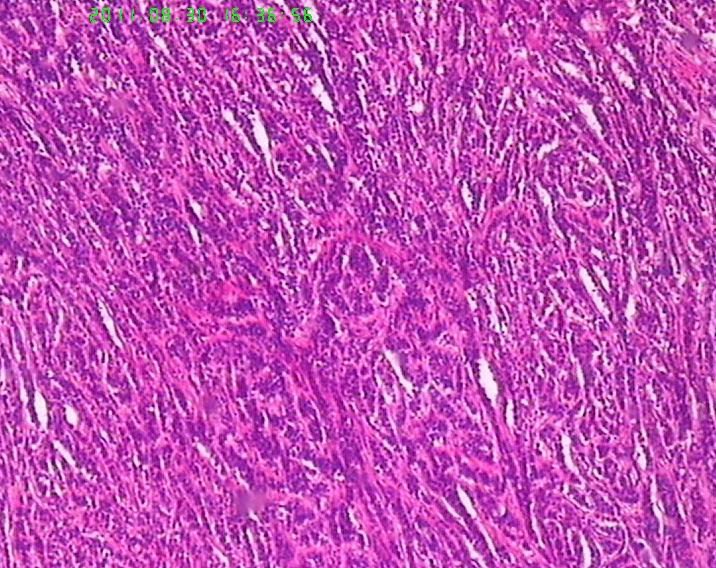

此例男,65岁。术前胃镜活检学生报告“低分化腺癌”,行手术治疗。术后见胃体后壁小弯测溃疡性肿物直径6.5cm,周围隆起质地硬,肉眼侵及肌层。镜下所见如图,似乎不是腺癌,是否是类癌??但核分裂很活跃,不见核仁。胃周淋巴结未检出转移。请老师们帮忙指正。学生感激。

低分化腺癌,不放心加做免疫组化。

低分化腺癌,不太像类癌